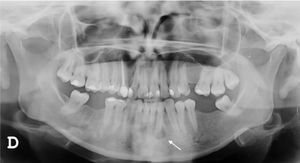

A 27-year-old female patient presented with a six-month history of a persistent and painful nodule on the chin. She referred occasional purulent exudate. There was no history of fever or systemic symptoms. Several courses of oral antibiotics had been ineffective. In the extraoral examination she presented an erythematous nodule with an important surrounding retraction (Fig. 1). Ultrasonography (Esaote MyLab Gamma®, 18 MHz) revealed a hypoechoic lesion with increased blood flow in the base and periphery. Moreover, an inflamed tortuous sinus tract extended through the subcutaneous tissue to the alveolar bone (Fig. 2). These findings were consistent with an odontogenic cutaneous fistula (OCF). A panoramic radiograph showed its origin in a mandibular incisor (Fig. 3). The patient was referred to the Maxillofacial Surgery Department of this hospital for assessment and treatment. Dental extraction was suggested in order to remove the source of the infection.

The diagnosis of OCF is usually made based on panoramic radiograph and computed tomography that show the damage of the alveolar process. However, these tests require considerable time and money to perform and may have side effects. Skin ultrasonography is a noninvasive and emerging technique with proven usefulness in localized lesions.3 High frequency imaging not only provides robust qualitative and quantitative information on skin lesions but also on their surrounding tissues. Moreover, color Doppler ultrasonography gives information about its vascularization. Therefore, this technique has been found really useful in the diagnosis of cutaneous sinus tracts. Ultrasound image of OCF consists of a hypoechoic linear but slightly tortuous sinus tract that reaches the cortical bone, with an increased blood flow in the peripheral regions of the tract.4,5 Most of these features characterize this lesion and easily distinguish it from other pathologies included in the clinical differential diagnosis. Regarding its treatment, antibiotic therapy brings an apparent healing, but if the source of infection is not eliminated, the sinus tract recurs in time. It is believed that high-frequency ultrasonography could also be useful in monitoring response to treatment by showing a decrease in the vascularization and a progressive reduction of the sinus tract. In addition, it could also allow the detection of early recurrences. In order to accomplish resolution, therapy has to focus towards the management of the dental infection, either with endodontic treatment or extraction.2 Surgical excision of the sinus tract is not usually necessary, as it heals spontaneously after the dental treatment.